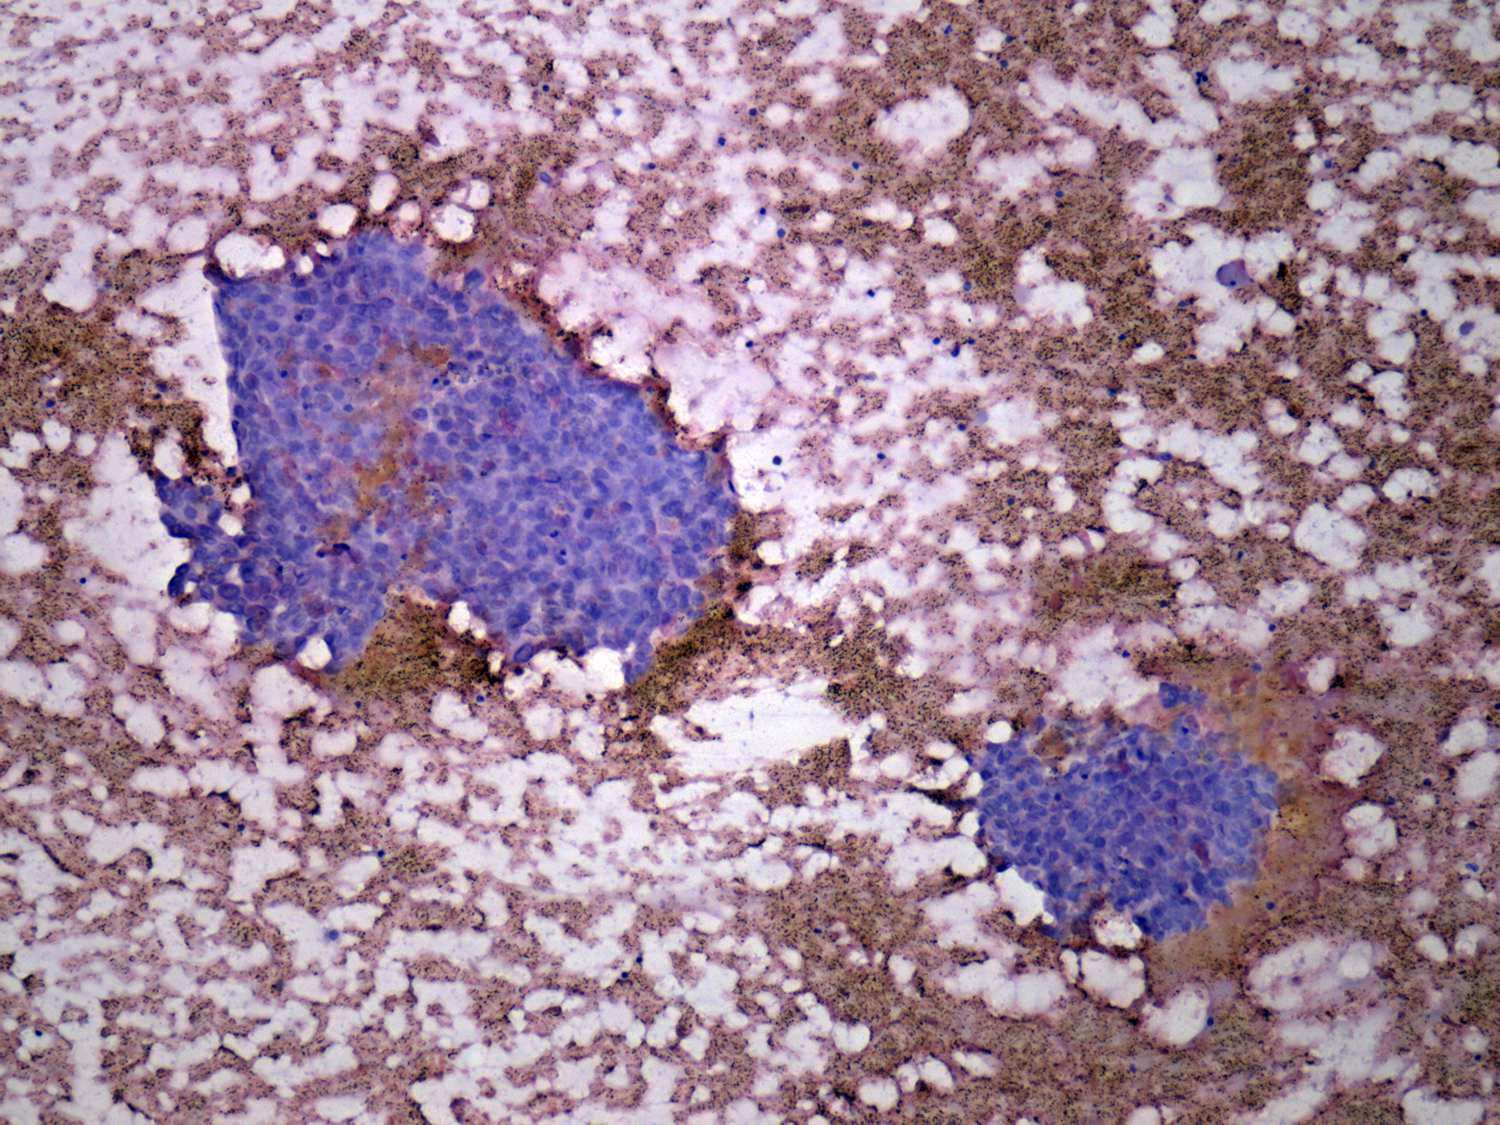

Intranodular hyperechogenic figures - case 401

(cytologic picture 1 of papillary cancer)

Pap-smear, 100x. Two papillary cell groups with nuclear crowding and overlapping.